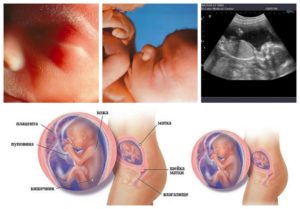

Матка

Показатель высоты стояния дна матки помогает врачу судить о течении беременности, соответствии темпов развития плода норме. В среднем на 19 неделе беременности дно матки находится на 17-20 см выше лонного сочленения.

- Матка становится еще больше, увеличивается ребенок, растет объем околоплодных вод. Масса матки составляет около трехсот граммов, а высота – до 20 сантиметров. Прощупать ее можно на один палец ниже пупка.

Четкие границы нормы окружности живота на 19 неделе отсутствуют. Этот показатель может зависеть от телосложения женщины, массы ее тела, размеров плода, количество вод. За среднее значение принято считать размер от 65 до 75 см.